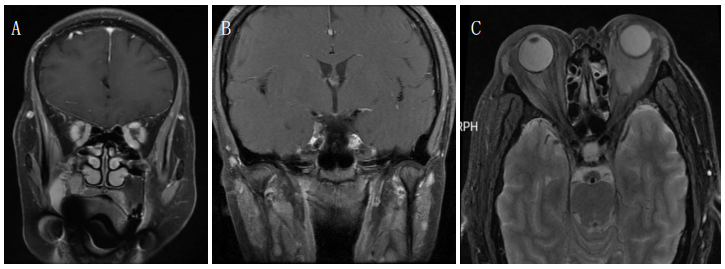

例3 患者,男性,65岁,因双眼复视、左侧眼球后疼痛20 d入院。查体:前节及眼底检查无异常,第一眼位右眼外斜,右眼内收受限,左眼上转、下转、内收均受限,头偏向左侧。患者双眼受累,且累及多条眼动神经,无视神经受累,定位在双侧海绵窦。眼眶MRI见双侧海绵窦增厚,左侧显著(图2A),诊断为Tolosa-Hunt综合征,予甲泼尼龙及他克莫司治疗。3个月后复查,患者双眼复视明显好转,眼部疼痛消失,双眼眼球各方向运动到位。

例4 患者,男性,57岁,因头痛、双眼复视、视力下降半年就诊。视力:右眼:光感,左眼:光感,双眼矫正视力无提高,眼前节及眼底检查无异常,双眼眼球各方向活动受限。患者既有视力下降传入症状,又有眼球运动障碍传出症状,定位在眶尖。实验室检查示:ESR 33 mm/h,ANA 1∶320,血清IgA 4.47 mg/L、IgE 165 kU/L,血管炎三项抗髓过氧化物酶(MPO)170 kU/L,其他感染、免疫学指标无异常。眼眶MRI见额底部、眶尖、海绵窦硬脑膜明显增厚,可见强化(图2B)。诊断为肥厚性硬脑膜炎,双眼压迫性视神经病变,抗中性粒细胞胞浆抗体(ANCA)相关性血管炎,予甲泼尼龙500 mg静脉滴注并序贯减量及他克莫司免疫抑制治疗,1个月后复查双眼视力右眼0.08、左眼0.06,头痛及复视明显好转。

例5 患者,女性,60岁,因双眼复视、流泪2个月入院治疗。视力:右眼1.0,左眼1.0,双眼眼睑肿胀,结膜水肿,眼底检查无异常,左眼上转受限,余各方向运动不受限。检验结果ESR 25 mm/h,ANA1∶320,抗U1-核糖核蛋白(U1-RNP)抗体219 AU/mL,甲状腺功能无异常,IgG4未见异常,其余感染、免疫功能指标均未见异常,眼眶MRI见左眼下直肌增粗强化(图2C),诊断为左眼炎性假瘤、结缔组织病。予甲泼尼龙冲击及他克莫司治疗后,双眼复视明显好转。

图 2 眼眶

MRI Figure 2 Orbital MRI

(A) 例 3 Tolosa-Hunt 综合征患者,增强冠状面 T1WI 示双侧海绵窦增厚;(B) 例 4 肥厚性硬脑膜炎、双眼压迫性视神经病变、ANCA 相关性血管炎患者,增强矢状面 T1WI 示额底部、眶尖部硬脑膜增厚;(C) 例 5 左眼炎性假瘤、结缔组织病患者,增强冠状面 T1WI 示左眼下直肌增粗。

(A)Case 3: Tolosa-Hunt sy ndrome, enhanced coronal T1WI showed bilateral cavernous sinus thickening , and left side was significant; (B)Case 4: hypertrophic durameningitis, bilateral compressive optic neuropathy, ANCA-associated vasculitis,enhanced sagittal T1WI showed thickening of the dura mater at the base of the forehead and the apex of the orbit; (C) Case 5: In patients with inflammatory pseudotumor and connective tissue disease, enhanced coronal T1WI showed thickening of the inferior rectus muscle of the left eye.